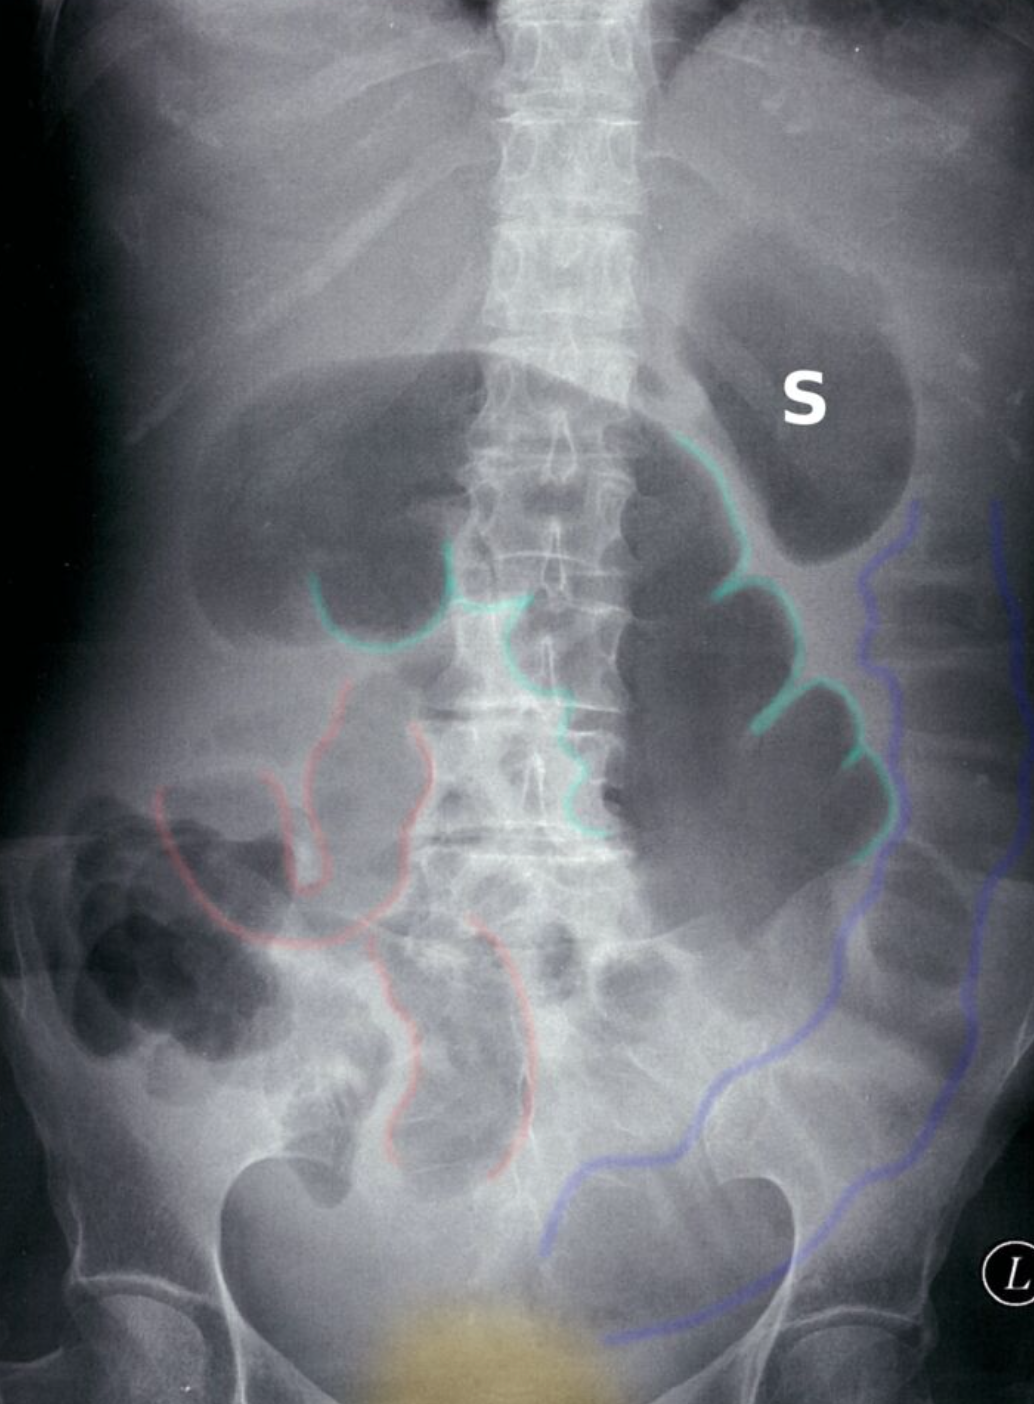

Dilated colon

X-ray abdomen (AP view; supine position) of a patient with a history of distal colonic obstruction

The transverse colon is dilated (green outlines) and distended loops of small bowel are present in the right lower quadrant (examples indicated by red outlines). Gas is present in the descending colon (blue outline), but no gas can be seen in the low pelvis in the region of the rectum (yellow overlay).

This radiographic appearance suggests distal mechanical obstruction or pseudo-obstruction in adynamic ileus. The acquisition of additional images (e.g., decubitus, prone) might help distinguish mechanical obstruction from pseudo-obstruction; the movement of gas would be restricted in obstruction and a transition point in the distal colon may be seen.